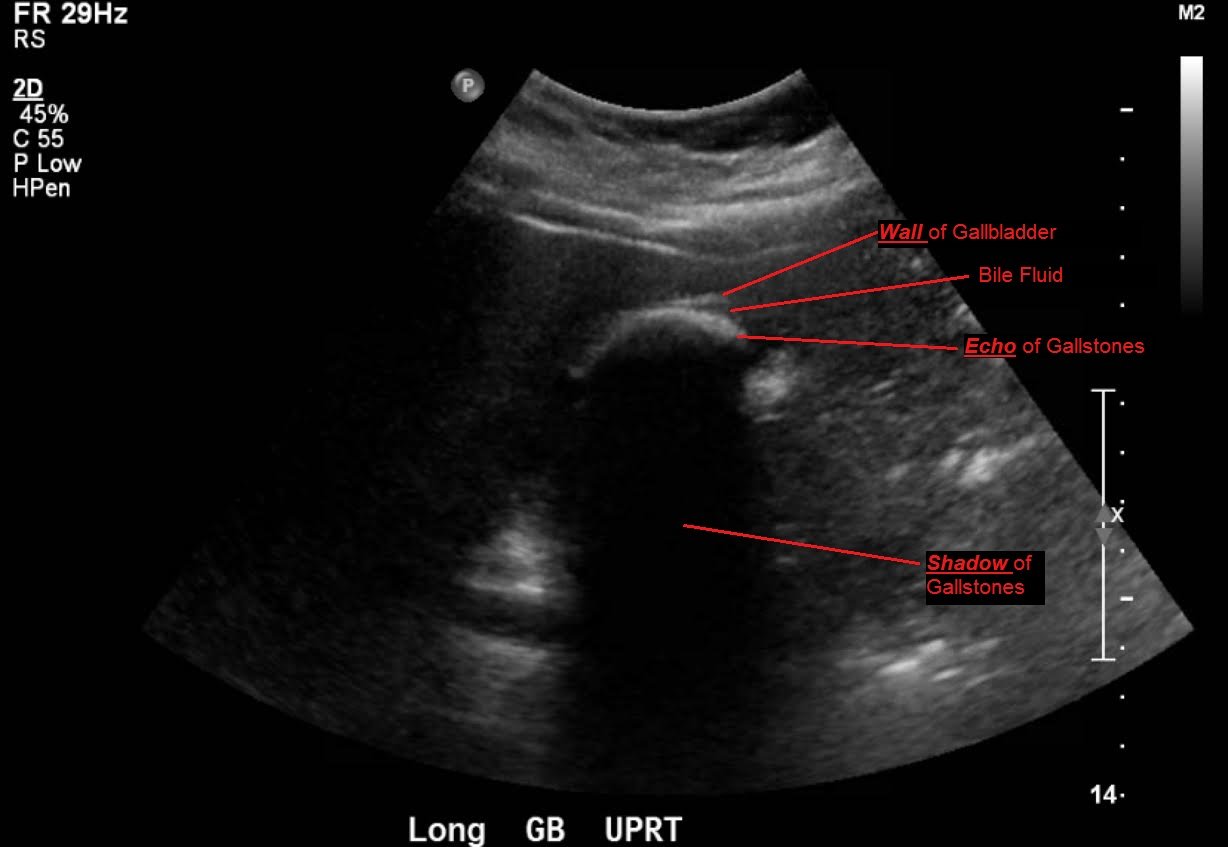

Cholelithiasis: WES Sign

Abdominal ultrasound showed the classic presentation of the Wall-Echo-Shadow (WES) sign. The superficial aspect of the gallbladder wall is represented by a hyperechogenic curve. Below this, bile fluid is represented by hypoechogenicity. Underneath the bile fluid is the echo of the dense border created by the collection of gallstones, represented by a hyperechogenic curve. Due to the high density of the gallstones, nothing deeper can be visualized (including other gallstones or the far end of the gallbladder); this is the shadow.

The WES sign, first described in the early 1980s, is a clear way of identifying cholelithiasis when the condition has progressed to fill the entire lumen of the gallbladder.1 In this case, the lumen of the gallbladder looks hypoechogenic relative to the surrounding tissue, much like an empty gallbladder. This is due to the border of the dense stones opposing the near wall of the gallbladder casting a shadow over everything distal to the stones. These key visualization techniques decrease non-visualization of chronic cholelithiasis.2,3,4 In most cases, WES sign is sufficient to diagnose cholelithiasis. Of note, “porcelain gallbladder” or collapsed duodenum can have the potential produce similar ultrasonographic findings.4,5